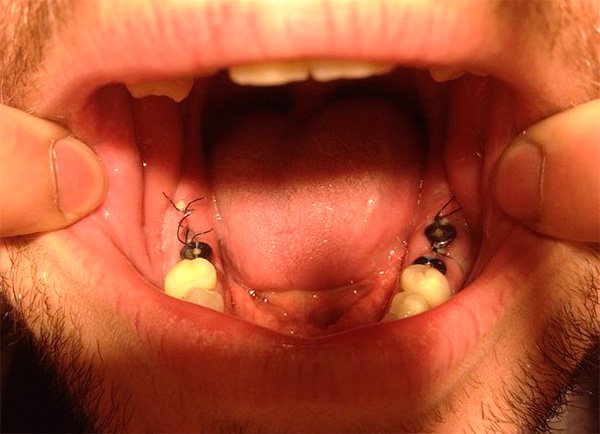

Пожалуй, стоит упомянуть также расхождение швов, нередко накладываемых на рану после имплантации. На нижеприведенном фото показан пример нормального состояния швов сразу после операции: